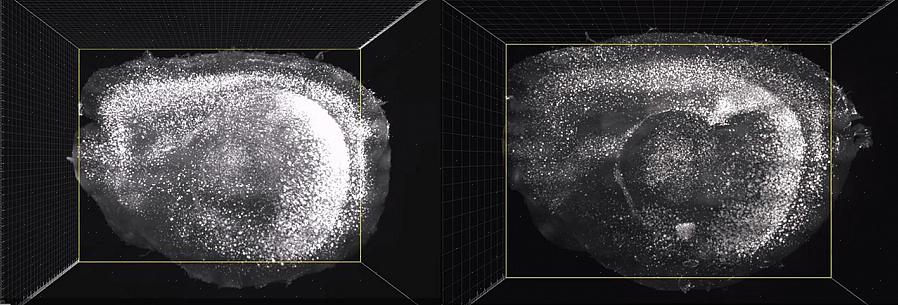

את הניסויים הוביל Li-Huei Tsai, מנהל מכון Picower ללמידה וזיכרון ב-MIT. הם כללו גירוי הפעילות של גלי הגמא של העכברים עם אלצהיימר באמצעות אור מהבהב ב-40 הרץ.

התוצאות גילו כי כמות הפלאק בטא עמילואיד וחלבון טאו פוספוריל ירד באופן דרסטי. לא רק זה, הגלים שיפרו את פעילות המיקרוגליה, התאים האחראים על ניקוי הפסולת במוח.

בניסוי ראשון זה, הם הגבילו את עצמם לגירוי פעילות הגמא של קליפת הראייה. עם זאת, הם רצו ללכת רחוק יותר. לפיכך, הם ניסו לעורר תנודות גמא על ידי חשיפה לצלילים של 40 הרץ. זה, בנוסף להפחתת כמות הבטא-עמילואיד בקליפת השמיעה, הפחית אותה גם בהיפוקמפוס. אולי אתה לא יודע את זה אבל האזור הזה הוא חיוני להיווצרות זיכרון.

לא מרוצים מהתוצאה, החוקרים החליטו לראות איזו השפעה תהיה לשילוב של שני סוגי הגירוי החזותי והשמיעתי. כתוצאה מכך, הם גילו שלא רק שהתוצאות היו חיוביות אלא היו מועילות פי שניים מכל אחת משיטות הגירוי בלבד. אפילו התגובה של המיקרוגליה הייתה הרבה יותר חזקה.